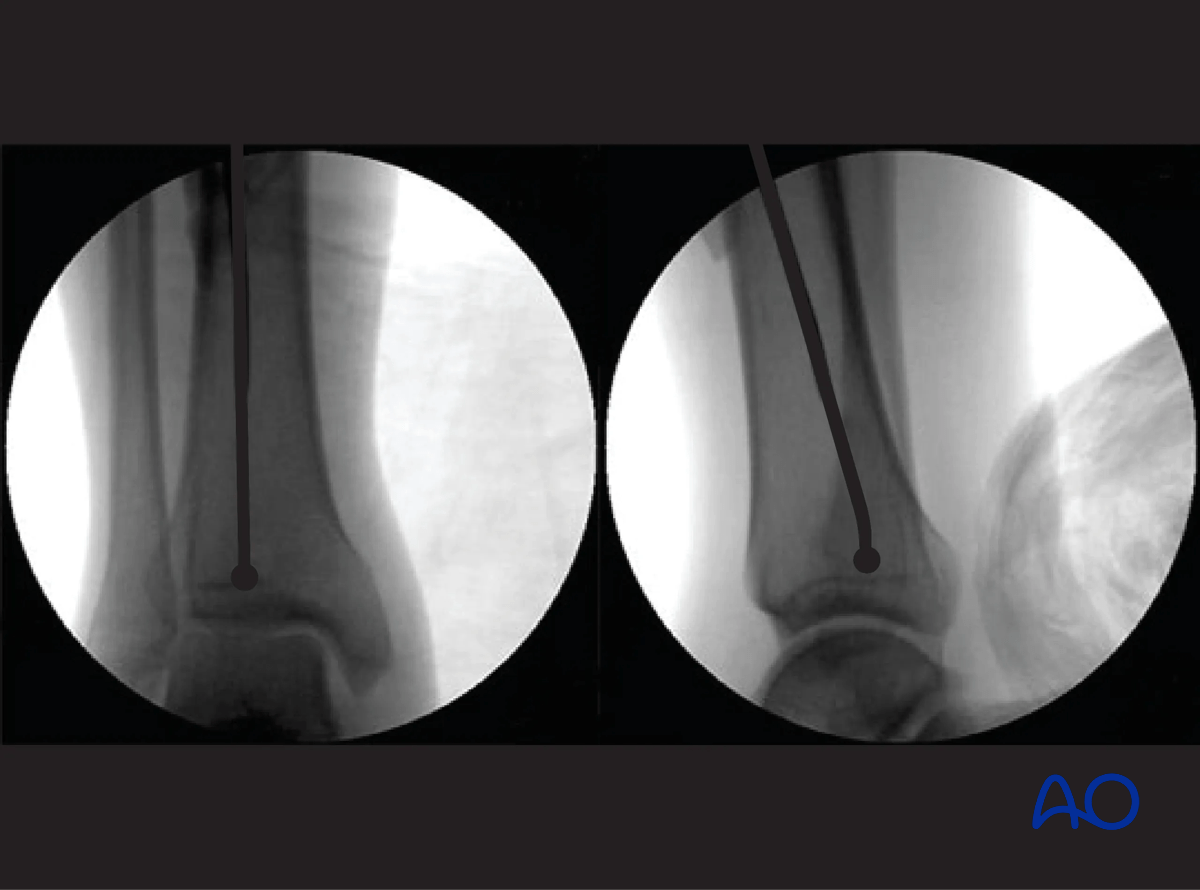

Fluoroscopic control

Use fluoroscopy to check that the guide wire is positioned above the center of the ankle joint.

Ensure a proper AP and lateral image of the ankle is taken. The end of the ball-tip guide wire should be seated at or just above the level of the epiphyseal scar. This is especially the case for more distal fractures of the tibia.

Tibia intramedullary nailing - fluoroscopic control